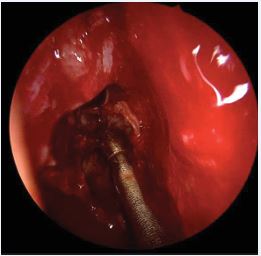

The olfactory mucosa of severe uncontrolled CRSwNP also presents typical markers of Type-2 inflammation (IgE, IL4, IL5, ECP, CCL3 and CCL4), similar to the pattern present in the nasal polyps. Patients post-Reboot demonstrated significant improvement in olfactory function, with significant response at just 1 month post-operatively and continued improvement at 2 years of follow-up. In contrast, ESS surgery showed improvement in olfactory function in the short-term follow-up, but worsened smell in the long term; Reboot also showed lower recurrence rates of nasal polyps when compared to ESS surgery at 2-year follow-up [17-24].Type-2 inflammation in nasal polyps is associated with worse impaired sense of smell before surgery but with a significant better olfactory improvement after Reboot. In other words, the more severe the Type-2 inflammation is in the polyps pre-operatively, the more significant the olfactory improvement is in the Reboot post-operative. There is no significant correlation between smell and Type-2 inflammation in the olfactory mucosa tissue, before or after surgery. Possibly, Type-3 inflammation in the olfactory mucosa is associated with better pre operative smell, but worse olfactory evolution after Reboot [24]. Postoperative nasoendoscopy images show that, by keeping the periosteum as intact as possible during surgery, the sinus mucosa re-epithelializes on average within 2 weeks, following with satisfactory long-term evolution (Figures 6 and 7).

Figure 6 Postoperative period of Reboot surgery at 2 weeks: return of nasal mucosa in the ethmoid sinus in 3 different patients. A) Left nasal cavity, reepithelization process; B) Left fronto-ethmoidal region, visualization of the frontal recess with adequate opening; C) Left nasal cavity, no signs of nasal synechia.